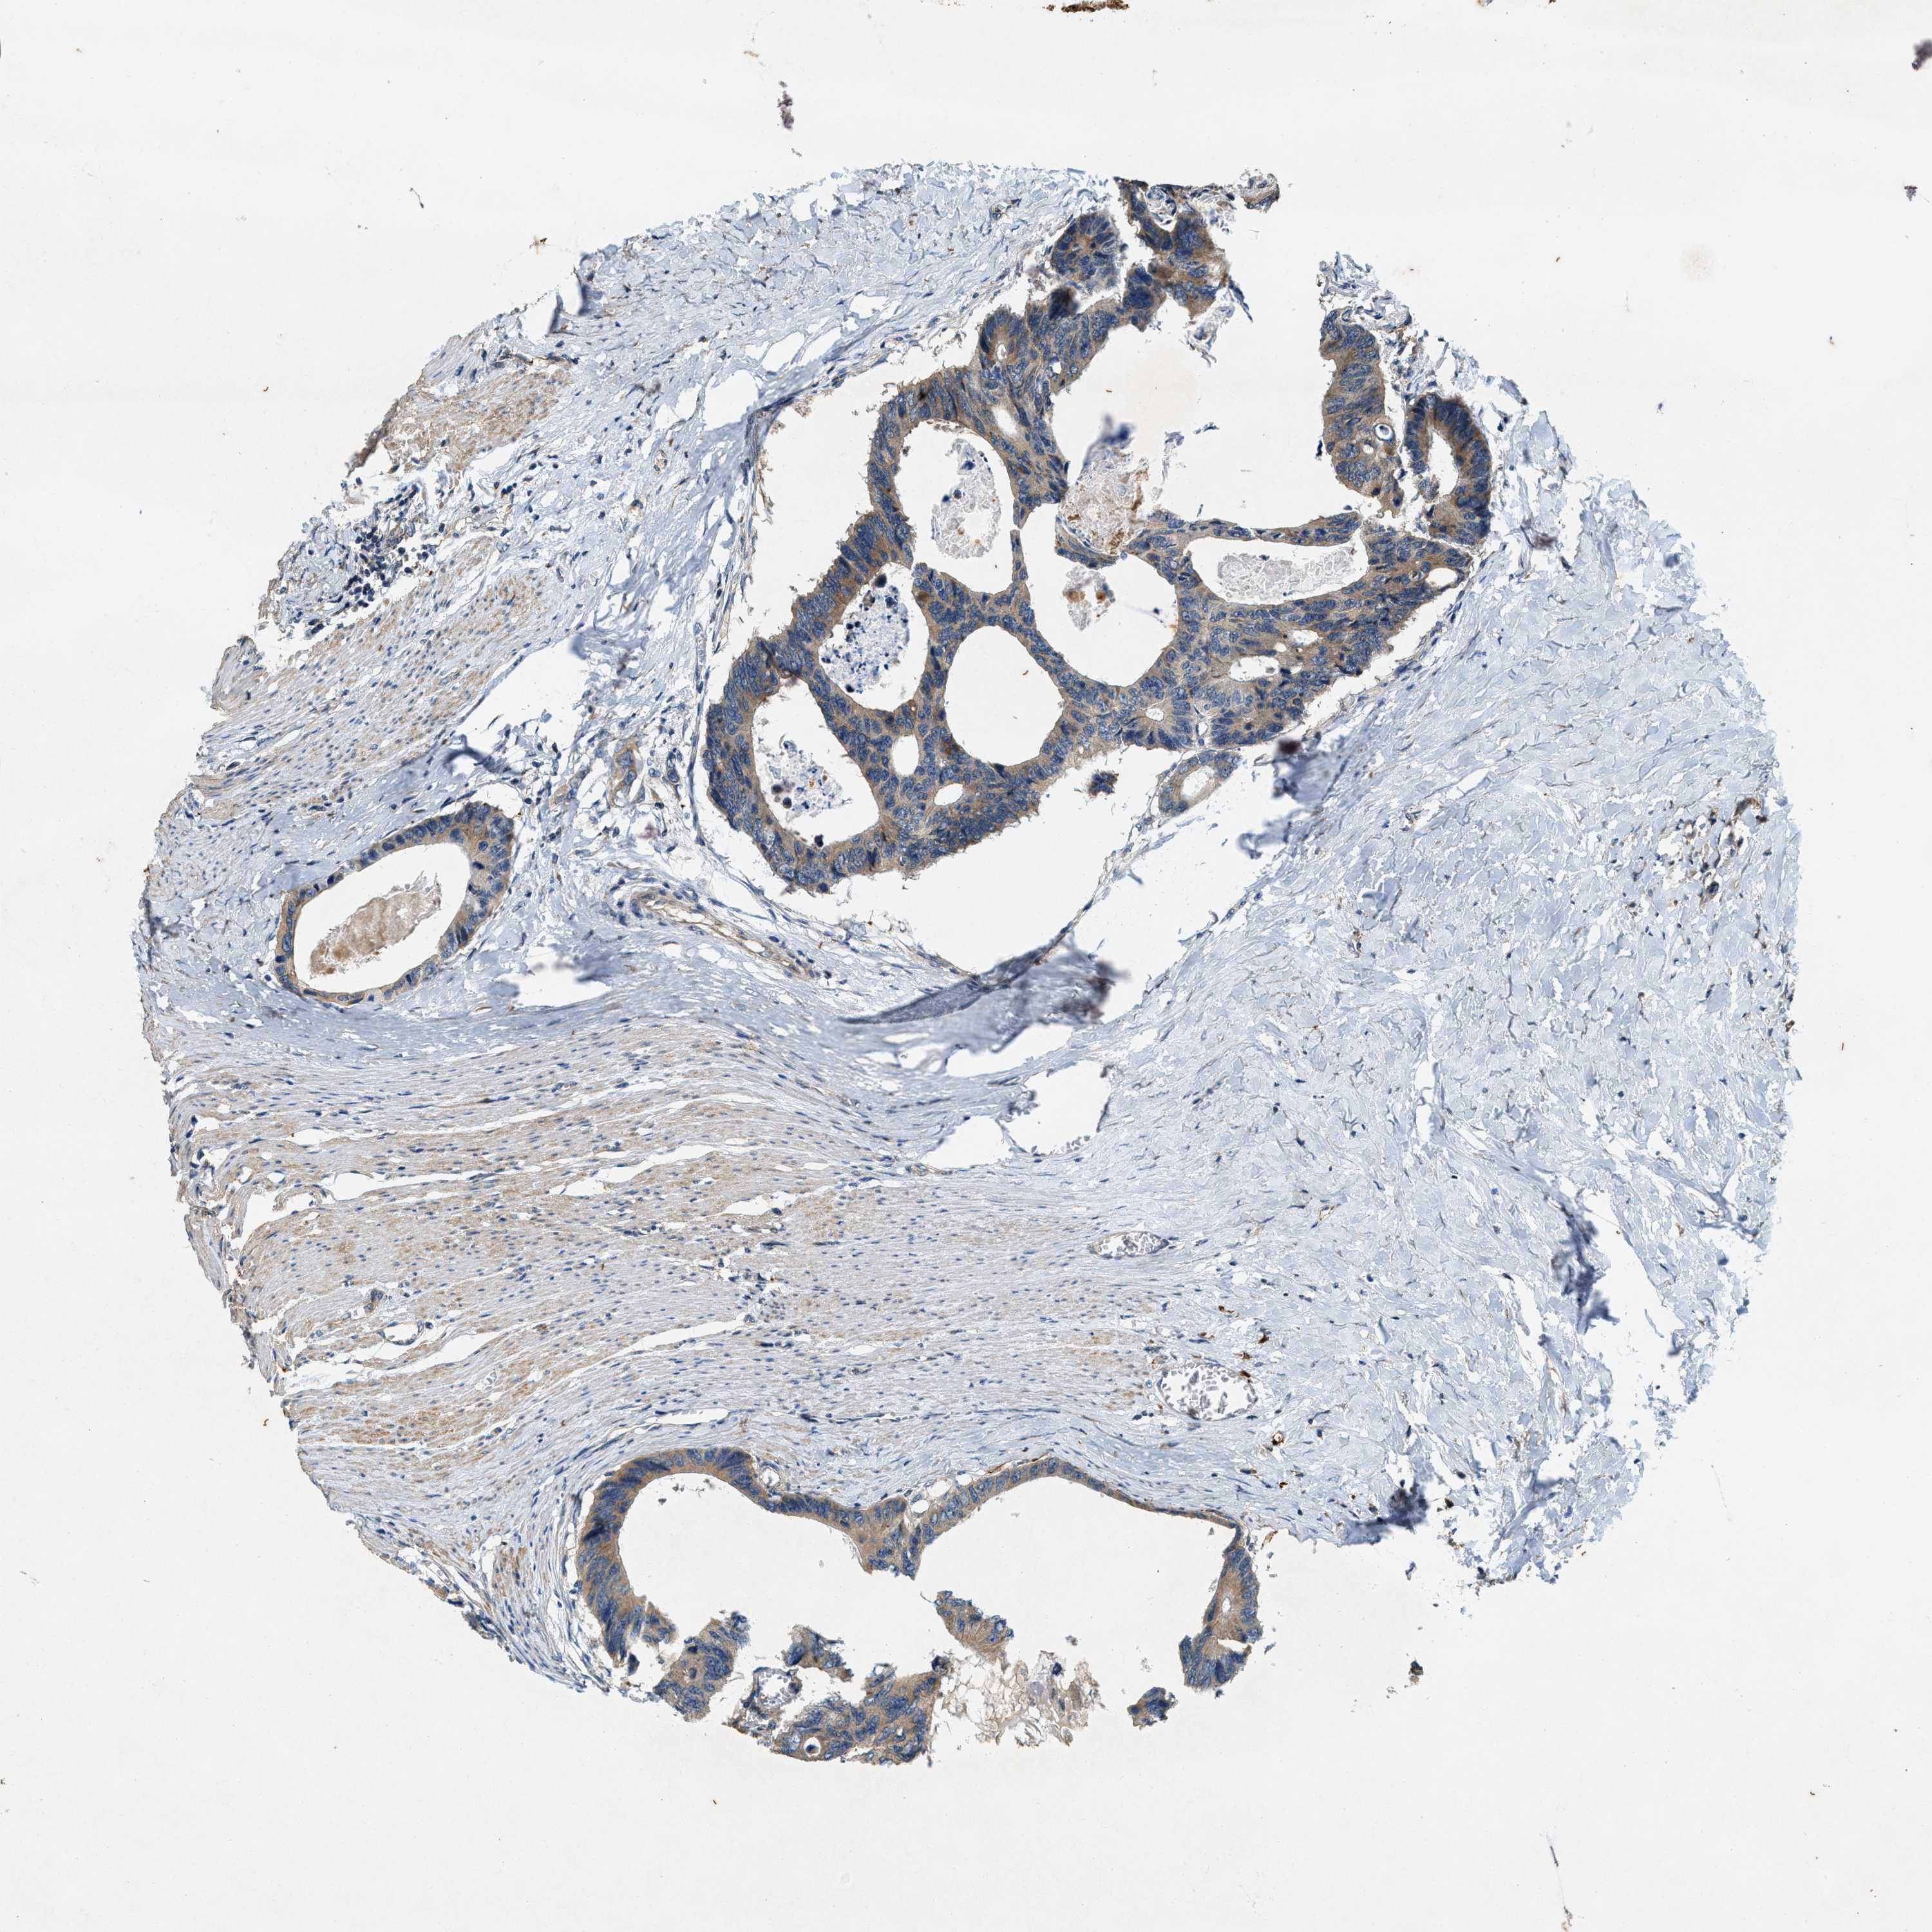

CANCER COLORECTAL CANCER Show tissue menu

Colorectal cancer

Rectum adenocarcinoma